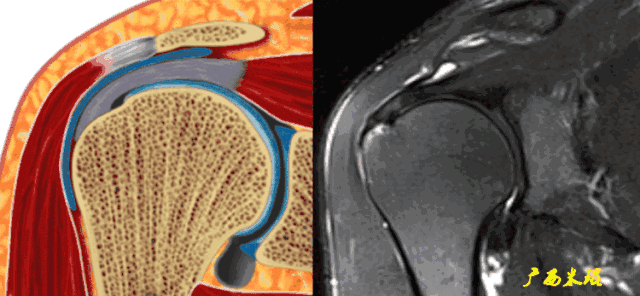

2、肩峰下滑囊炎

肩峰下滑囊是一个非常重要的解剖结构,大部分肩关节的病变都会波及,肩袖损伤更不例外,同时,肩峰下滑囊炎的病变也可以波及到肩袖等组织。肩峰下滑囊炎在MRI上表现是非常明显的,如果其正常,肩袖一般也正常。

a、肩峰下滑囊增大,是肩袖损伤必有的表现。

b、肩峰下滑囊贯通(与关节腔相通),预示着肩袖的完全撕裂。